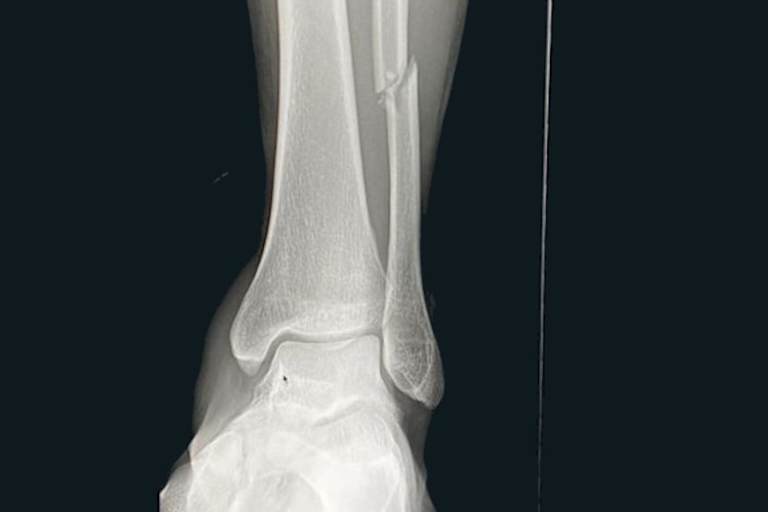

Brenner bekam einen Schlag auf den Kopf, konnte das Rennenwochenende aber fortsetzen. Schlimmer erwischte Booth-Amos: Mit einem gebrochenen Wadenbein war das zweite Saisonmeeting für den ehemaligen Moto3-Piloten gelaufen. "Es tut mir sehr leid, wie es gelaufen ist. Ich war mir sicher, dass wir auf dieser Strecke gut hätten abschneiden können, tatsächlich hatte ich eine gute Pace und erholte mich gerade, als ich von einem anderen Fahrer getroffen wurde", schilderte der Kawasaki-Pilot den Unfallhergang aus seiner Sicht. "Leider ist das Wadenbein bei dem Sturz gebrochen. Ich werde mich schnellstmöglich operierenlassen, um für Estoril wieder fit zu sein." Die Fixierung des gebrochenen Wadenbeins mit einer Metallplatte erfolgte bereits zu Wochenbeginn; die Teilnahme von Booth-Amos am dritten Rennwochenende in Estoril am 20. bis 22. Mai ist nicht gefährdet.